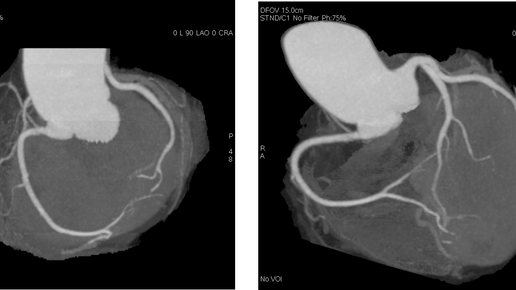

Поучительная история моего клиента: Если бы не сдал — меня бы уже не было Я даже не подозревал, что этот анализ покажет то, что может убить за 2 секунды. Ничего не болело. Работал, ездил, пил кофе. Да, уставал. Да, сердце иногда будто ёкало. Но кто не устаёт в 55? Подумал — просто возраст. Оказалось, не возраст. А бомба с таймером, которую я сам себе откладывал. Рассказываю, как дошёл до этого анализа, что он показал — и почему теперь советую его каждому другу и даже соседу по даче. Первые «звоночки»...